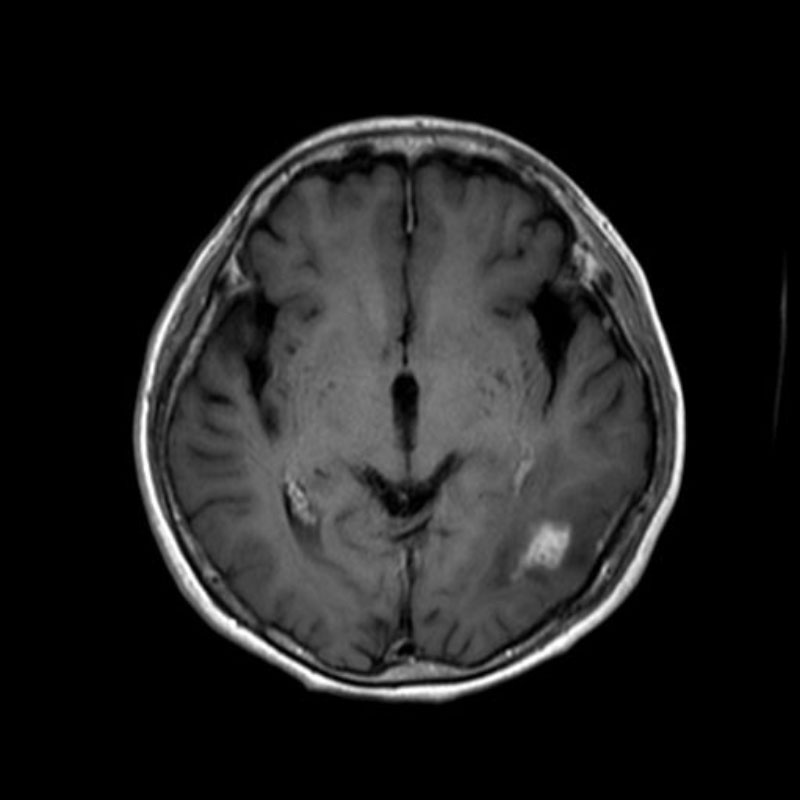

断層撮影

No.’25_45 手術前1

No.’25_45 手術前2